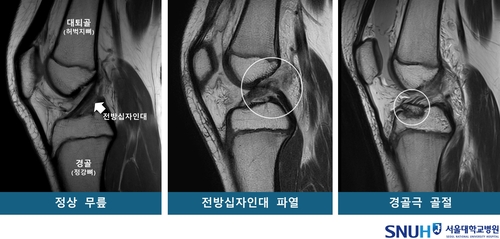

[서울대병원 제공][서울대병원 제공]청소년들이 운동하다가 무릎이 다쳤을 때 전방십자인대가 파열될지, 경골극(脛骨棘)이 골절될지는 타고난 무릎 모양에 따라 달라진다는 연구 결과가 나왔습니다.

연구팀은 이들을 각 53명씩 전방십자인대 파열군, 경골극 골절군, 정상군으로 나누고, 3차원 영상을 바탕으로 14개 해부학적 지표를 분석했습니다.

전방십자인대 파열은 말 그대로 인대가 '뚝' 하는 소리를 내며 찢어지는 부상이고, 경골극 골절은 전방십자인대가 인대에 붙은 무릎뼈(경골극)를 잡아당겨 떨어져 나가는 부상입니다.